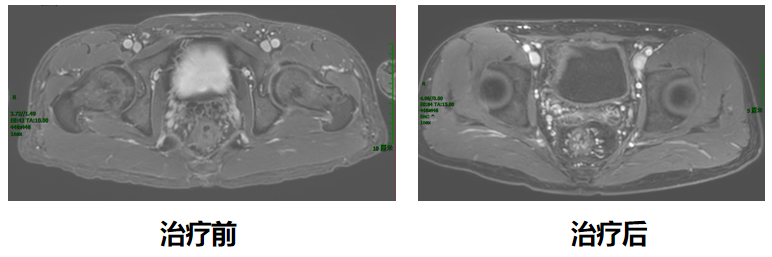

今年33岁的小江(化名)是接受该创新治疗模式的患者之一。2023年9月,小江在协和医院确诊为低位直肠腺癌T3N2M0,肿瘤下缘距离肛门口仅2厘米,保肛难度确实非常大。

经过胃肠外科、腹部肿瘤科、影像科、病理科等多学科讨论后,最终决定采用短程放疗序贯化免联合全新新辅助治疗。2023年9月,小江接受了5次直肠病灶及淋巴结引流区放疗,随后进行化疗联合免疫新辅助治疗。今年1月,再次复查肠镜发现,他的直肠下段肿瘤病灶已经消失,获得了临床完全缓解。这也意味着小江的肿瘤术前完全消退,后续接受规范的监测和复查即可。